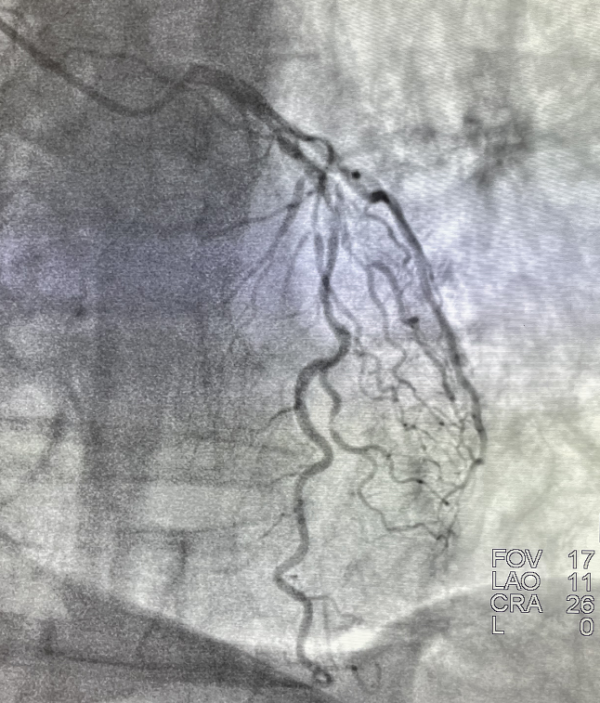

2022年1月8日,山東第一醫科大學附屬省立醫院心內科成功為一例嚴重冠脈鈣化病變患者進行了準分子鐳射斑塊消蝕術(ELCA),並順利植入冠脈支架,腔內影像顯示支架膨脹貼壁良好,未見夾層血栓。

據醫院心內科苑海濤主任介紹,ELCA利用光化學、光熱、光機械原理,形成光脈衝、聲波、空化氣泡對纖維鈣化病變、血栓等起到消融與鬆解修飾進行,使支架更容易輸送,有利於支架充分擴張,並避免無複流或遠端栓塞等問題,使得複雜冠脈病變患者得以成功進行冠脈介入治療。目前ELCA通常用於支架內再狹窄、支架擴張不良、重度鈣化病變、球囊不能透過的病變、慢性完全閉塞、靜脈橋血管狹窄的患者。